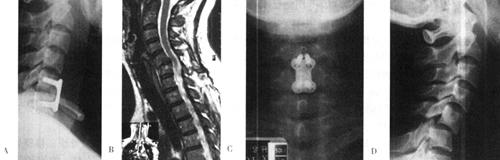

手术采用标准Smith-Robinson横切口,在颈4水平从颈部血管神经鞘和内脏鞘之间进入,显露颈长肌,并向上剥离直至颈2/3椎间隙。切开颈2/3椎间盘前部纤维环,显露颈2椎体的前下缘终板。在C臂引导下,在颈2椎体前下方正中准确地钻入1枚头端带螺纹的克氏针,直至齿突尖部(图13-15、图13-16)。注意保护椎体进针处骨皮质的完整性,过度地破坏骨质很容易使固定螺钉滑出。用.直径2.5mm中空的钻头通过克氏针的引导进行钻孔,然后用中空丝锥进行攻丝。准确量出克氏针的长度,拧入直径3.5mm中空螺钉。如果用2枚螺钉固定,可分别从旁开中线3~4mm处进钉,对准齿突尖部小心钻入,并向齿突中线靠拢汇聚(图13-17)。

图13-15 齿状突螺钉操作示意(A.钻入克氏针;B.扩孔;C.D.拧入螺钉)

图13-16 单枚螺钉固定齿状突骨折术后X光片

图13-17 两枚螺钉固定齿状突骨折

术后第二天可起床活动,戴颈托6~12周。Aebi等报告齿状突加压螺钉的并发症:复位欠佳者占19%,骨折不愈合假关节形成者占12%。